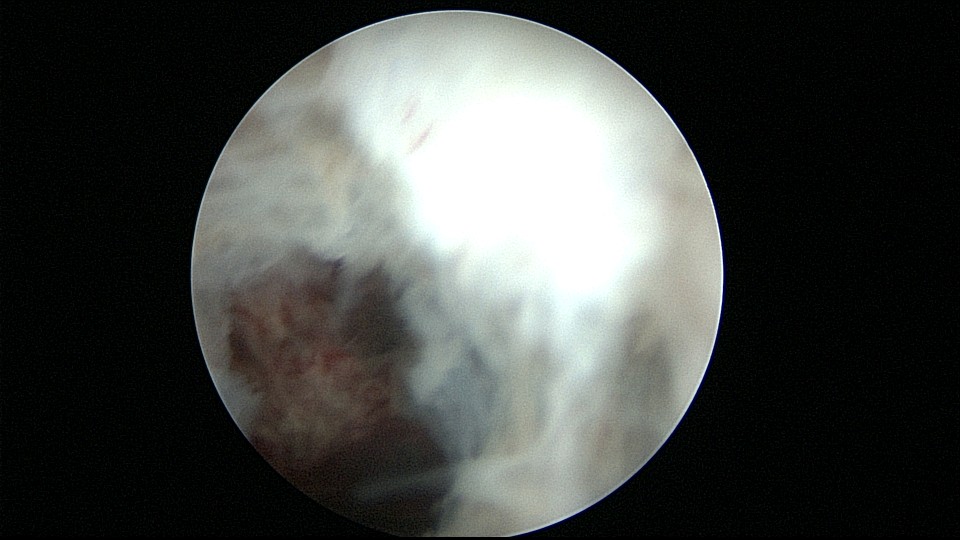

患者25岁,G1P0,停经52天,稽留流产,B超宫内偏右查见大小约2.4cmx1.0cmx1.7cm孕囊回声,形态规则,内可见直径约0.4cm的卵黄囊回声,未见胎芽,孕囊旁肌层最薄处厚约0.5cm,子宫中下段回声连续性欠佳,似可见一分隔回声。2021年7月宫腔镜探查,胚胎着床于宫腔前壁偏右,宫颈内口及宫腔左侧壁粘连。清除妊娠组织,单极电针分粘,恢复宫腔形态,双侧输卵管开口显露(第一次怀孕,宫腔粘连原因?)。2022年7月自然妊娠,2023年3月足月剖宫产分娩。2024年12月,外院人流术后1+月,宫内残留,与后壁肌层分界欠清,局部血流信号增多,到我院宫腔镜切除残留组织(后3张图片)。现患者30岁,G3P1。宫腔粘连常常不能阻止妊娠,但胚胎停育发生率增加。